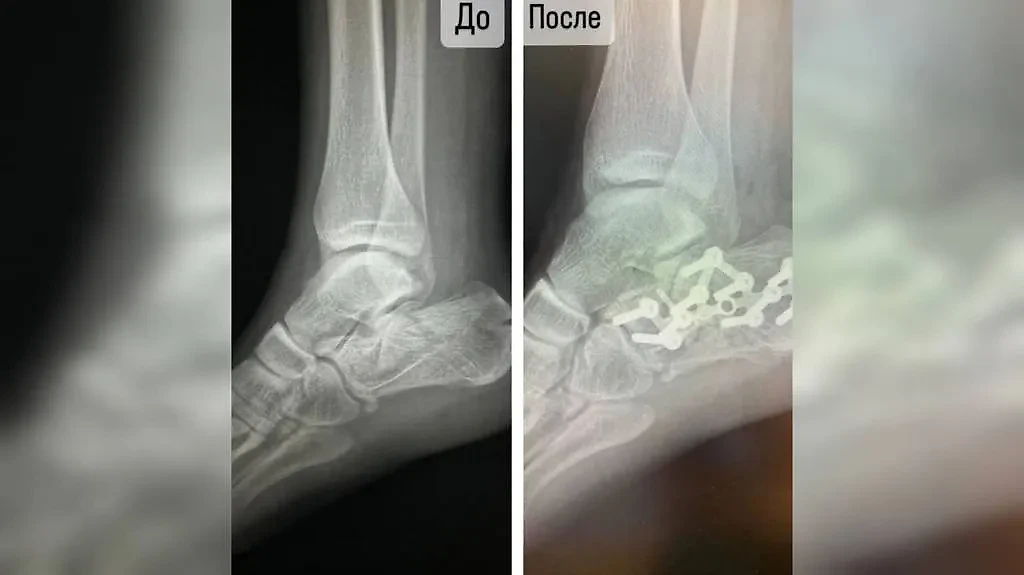

Пациентку привезли в больницу Волоколамска с жалобами на сильную боль в обеих ногах, из-за которой она уже не могла ходить. Рентген показал закрытые оскольчатые переломы обеих пяточных костей, а также выявил смещение отломков. Всё это — последствия прыжка в воду с высокого берега.

"Мы выполнили операцию на обе ноги с применением методики костной аутотрансплантации — одного из наиболее эффективных на сегодняшний день методов остеопластики. Его преимущество заключается в снижении к минимуму вероятности отторжения костного блока, ведь в качестве донора для него выступает сам пациент. Собственная ткань приживается очень быстро, а установленные в неё импланты служат не меньше, чем смонтированные в натуральной, не оперированной кости", — поделился деталями операции завотделением сочетанной травмы Василий Козлов.

Рентген ноги девушки до операции и после неё. Фото © Минздрав Московской области